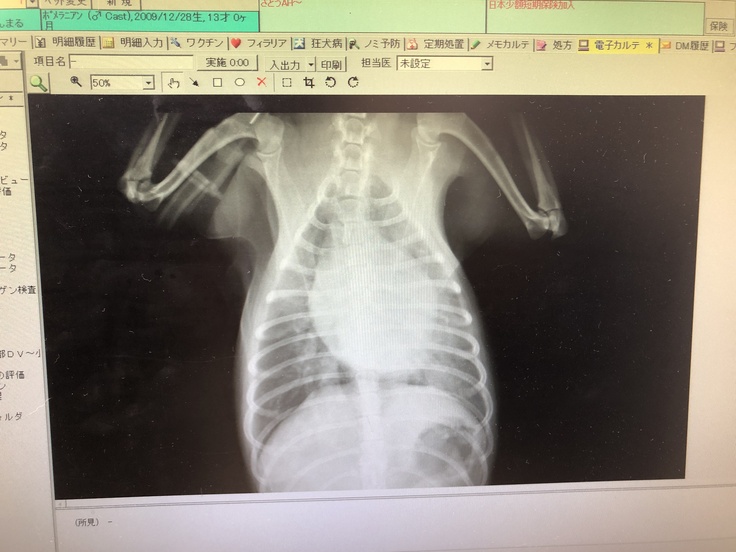

結果としては僧帽弁閉鎖不全症になり肺水腫も発症していました。さらには肺炎の合併症にもなっていました。

専門医の診察結果もやはり僧帽弁閉鎖不全症でステージ※はC(心不全の状態にいる)。余命としては平均半年~9ヶ月と言われました。

※ステージA、B1、B2、C(肺水腫)、D(治療困難)

※血液検査などの結果です。炎症マーカーの数値が高く、利尿剤により腎臓の数値が上がっています。また心臓に送られる血液の逆流が止まりません。

僧帽弁閉鎖不全症とは、心臓の弁のひとつである僧帽弁がきちんと閉じなくなる病気です。さらに肺に水が溜まり肺水腫を引き起こすと、呼吸していてもうまく空気を取り込めず、心不全を起こします。 僧帽弁閉鎖不全症が進行すると、血液をうまく送り出せなくなって心臓の中で渋滞が起き、うっ血性心不全になります。 さらに重症になると、肺水腫(肺に液体がたまり、酸素と二酸化炭素の交換がスムーズにいかなくなるため、呼吸が苦しくなる病気)や呼吸困難、チアノーゼ(舌の色が紫色になる)などの症状を起こし、死に至る場合もあります。 出典元※NEWHEARTワタナベ国際病院https://newheart.jp/glossary/detail/cardiovascular-surgery_003.php※みんなの動物病気大百科https://www.anicom-sompo.co.jp/doubutsu_pedia/node/904